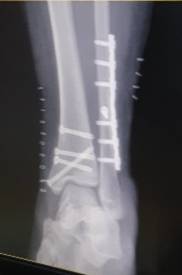

나 수술했는데 이 정도면 교통사고 급 아니니?(사진주의)

ㅋㅋㅋ교통사고 아니냐고ㅋㅋㄱㄱ

헉 어쩌다 다쳤어

5년 전

글쓴이

혼자 넘어짐;

놀랍게도 제자리에서 평지에서 저리 되었댜... 재수가 없었던거지